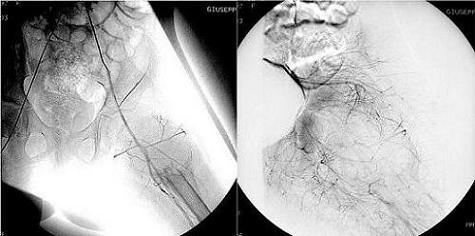

Arteriografia della lesione. A sinistra: immagine non sottratta. A destra: arteriografia della lesione dopo embolizzazione.

Embolizzazione curativa: Arteriografia della lesione. A sinistra: immagine non sottratta. A destra: arteriografia della lesione dopo embolizzazione.